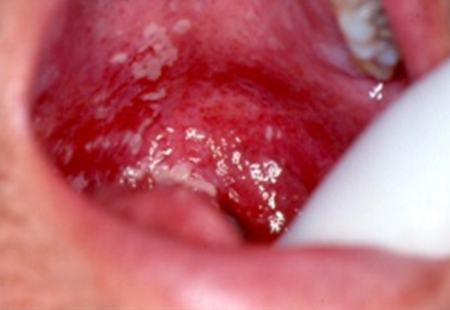

Инфекция, вызванная вирусом герпеса, проявляющаяся в виде болезненных язв, покрытых псевдомембранами на правой стороне спинки языка. Диагноз установлен в течение третьей недели лучевой терапии при лечении рака гайморовой пазухи. Получена реакция на ацикловир

Из коллекции профессора Ourania Nicolatou-Galitis